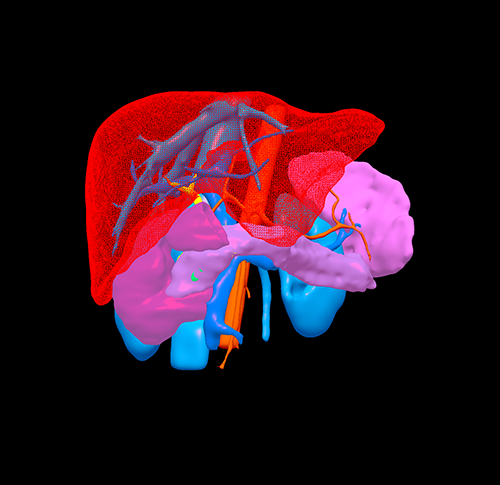

胰腺头颈假性乳头状瘤 -胰腺中段切除